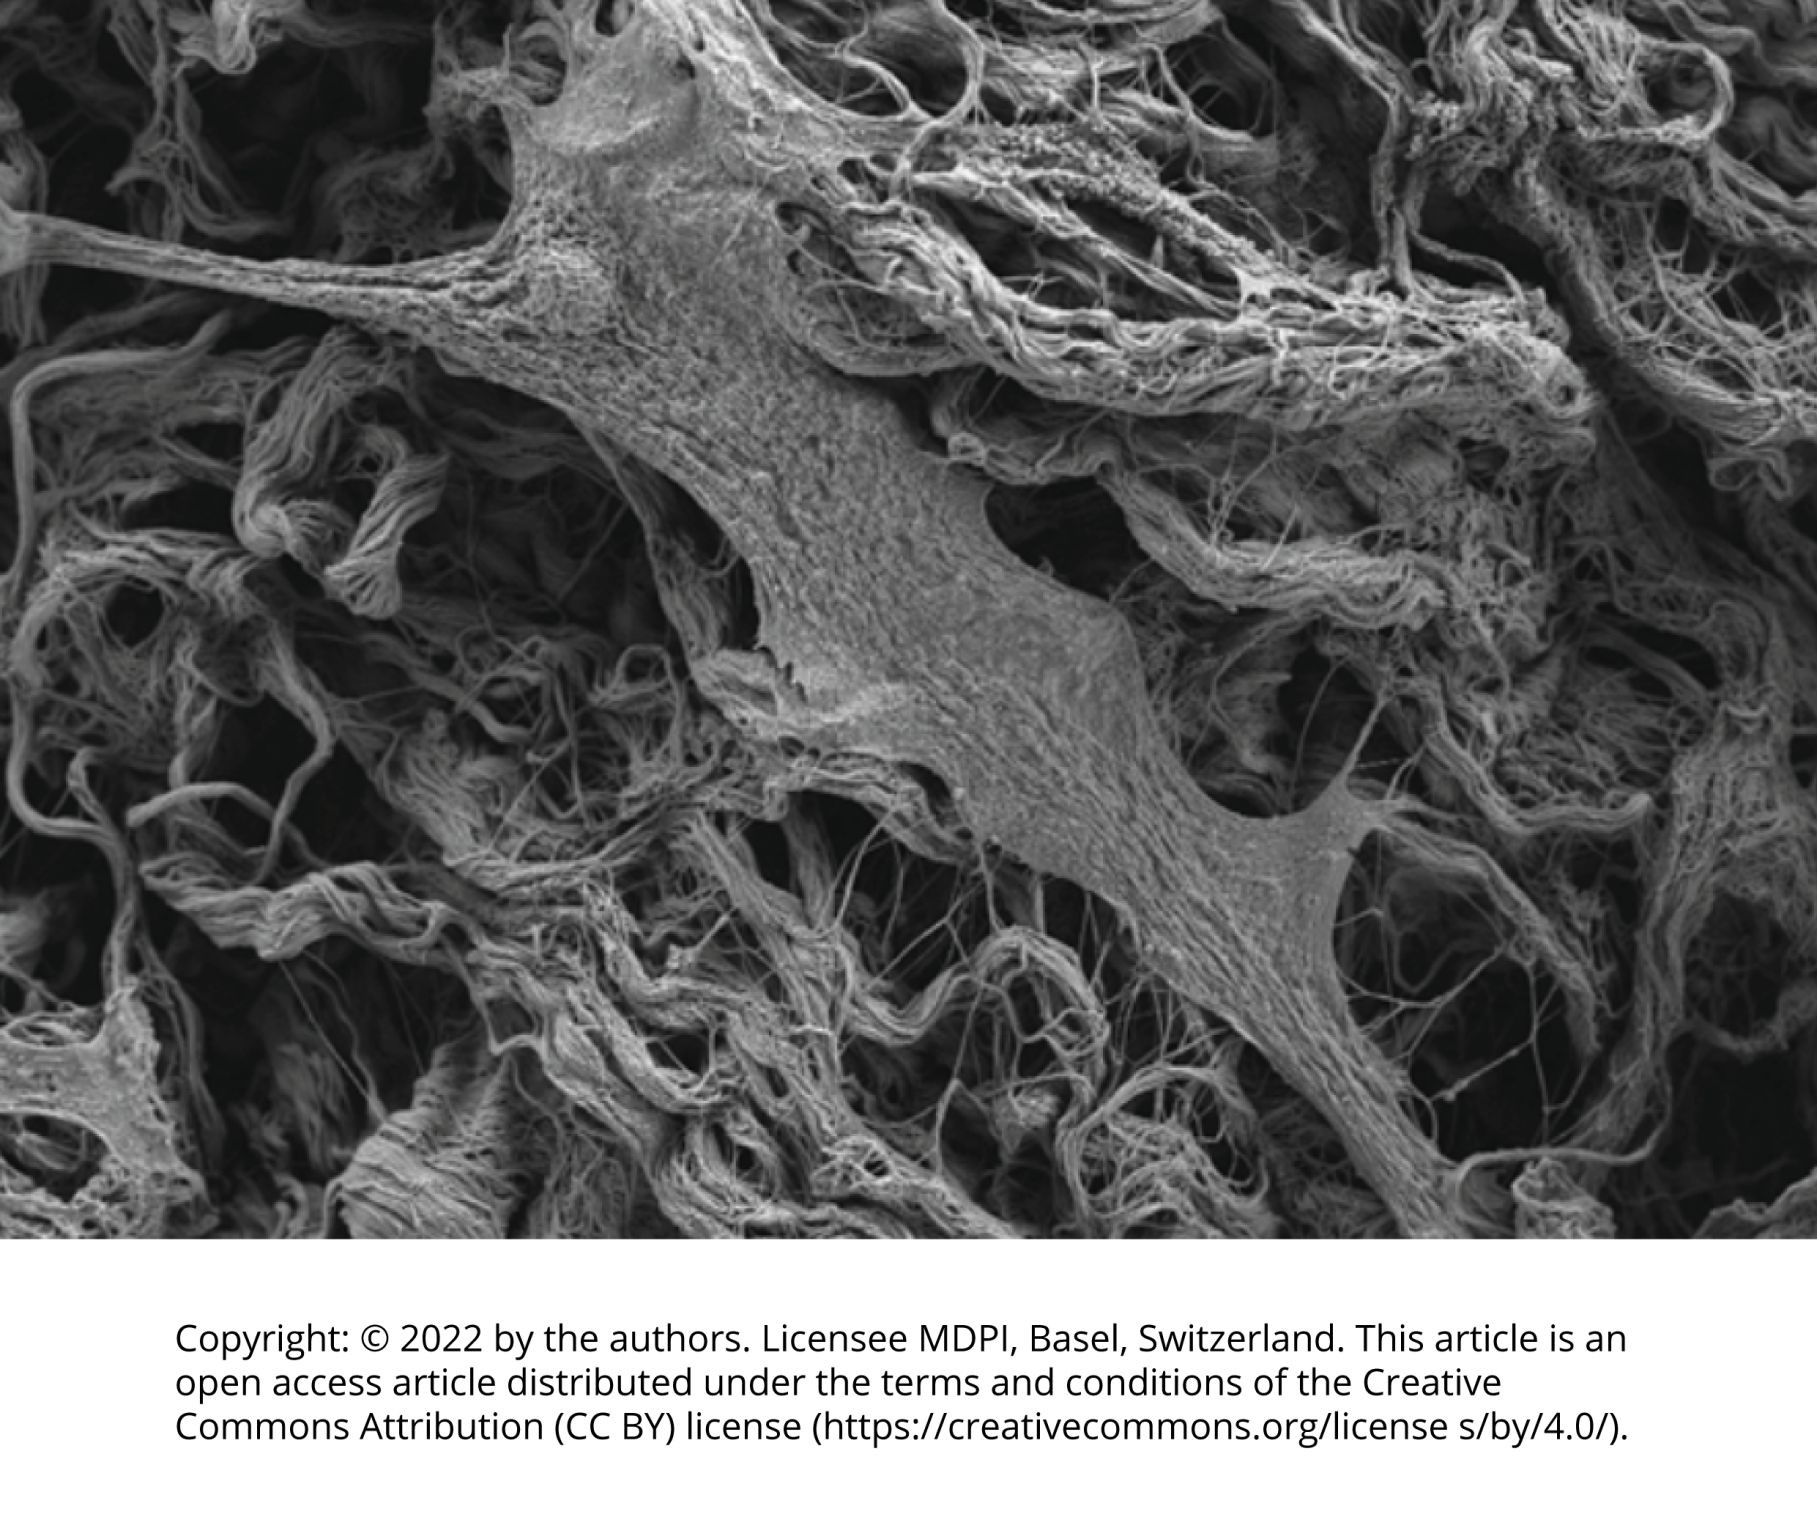

Membrany osierdziowe SHELTER S, dzięki procesowi sieciowania, mają wyjątkowe właściwości wytrzymałościowe. Dzieje się tak ze względu na większą liczbę wiązań wewnątrzcząsteczkowych pomiędzy włókienkami kolagenowymi.

Membrany są wysoce biokompatybilne i stymulują proliferację komórek w statystycznie istotny sposób zarówno na powierzchni, jak i w teksturze materiału.

Badania in vitro wykazały, że membrana SHELTER® jest wysoce hydrofilowa, co oznacza, że jest w stanie szybko wchłonąć roztwór, z którym wejdzie w kontakt, zachowując jednocześnie swoją trójwymiarową strukturę (bez zapadania się). Po uwodnieniu membrany uzyskują wysokie właściwości adhezyjne i dopasowuje się do powierzchni: jest to niezwykle ważne w przypadku zastosowań, w których membrana musi być stosowana i dopasowywać się nawet do bardzo nierównych powierzchni.

SHELTER S (zdjęcie płaskie, 10μm)